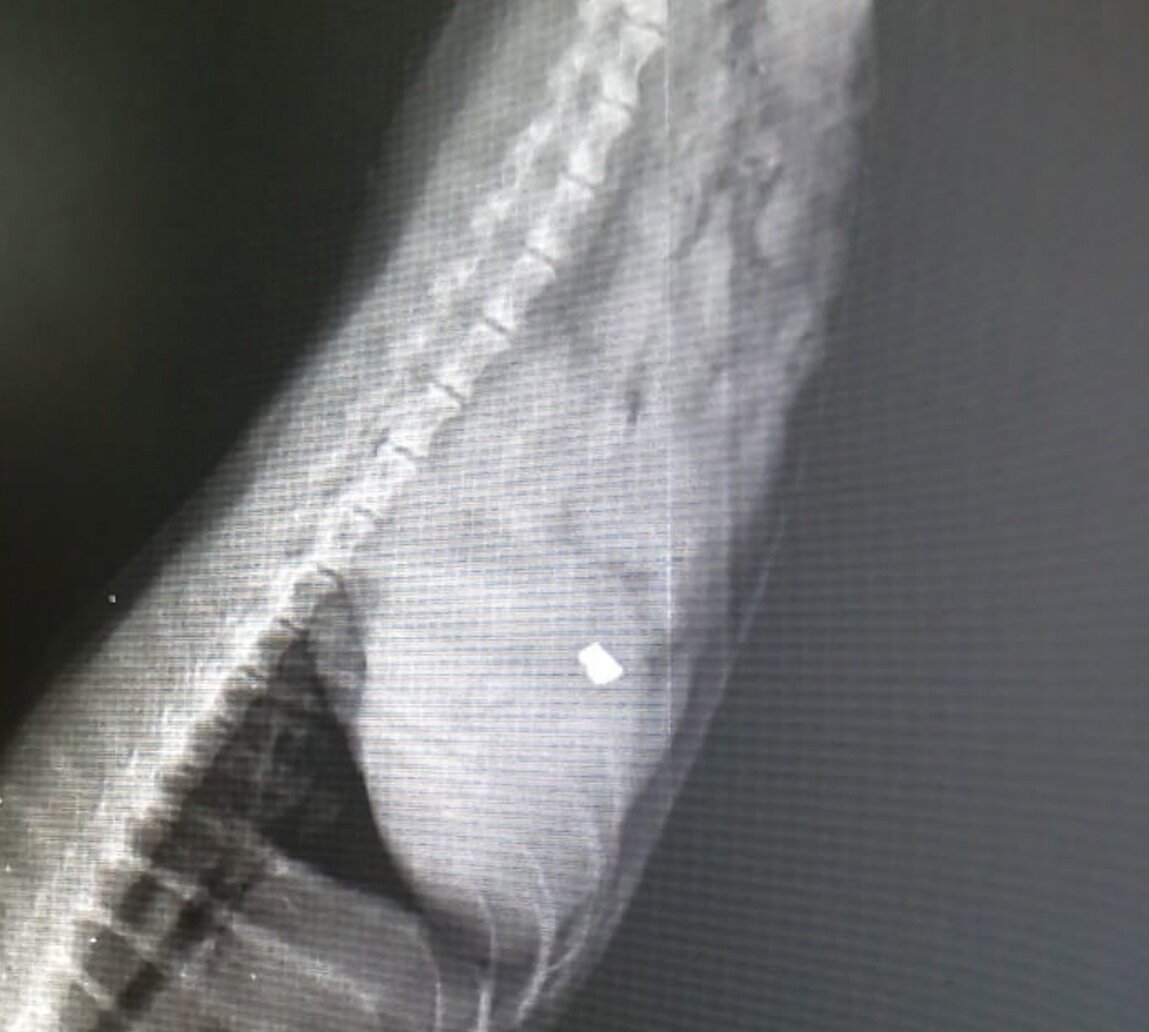

Инородный регнтгенконтрастный предмет в области желудка

Малыша принесли на прием с рвотой. Рассказали всю предысторию, и конечно же мы сделали рентген. А там...

Конечно же нужно максимально быстро извлеч предмет. Благо гастроскоп есть в наличии.

После некоторых манипуляций предмет удалось достать.